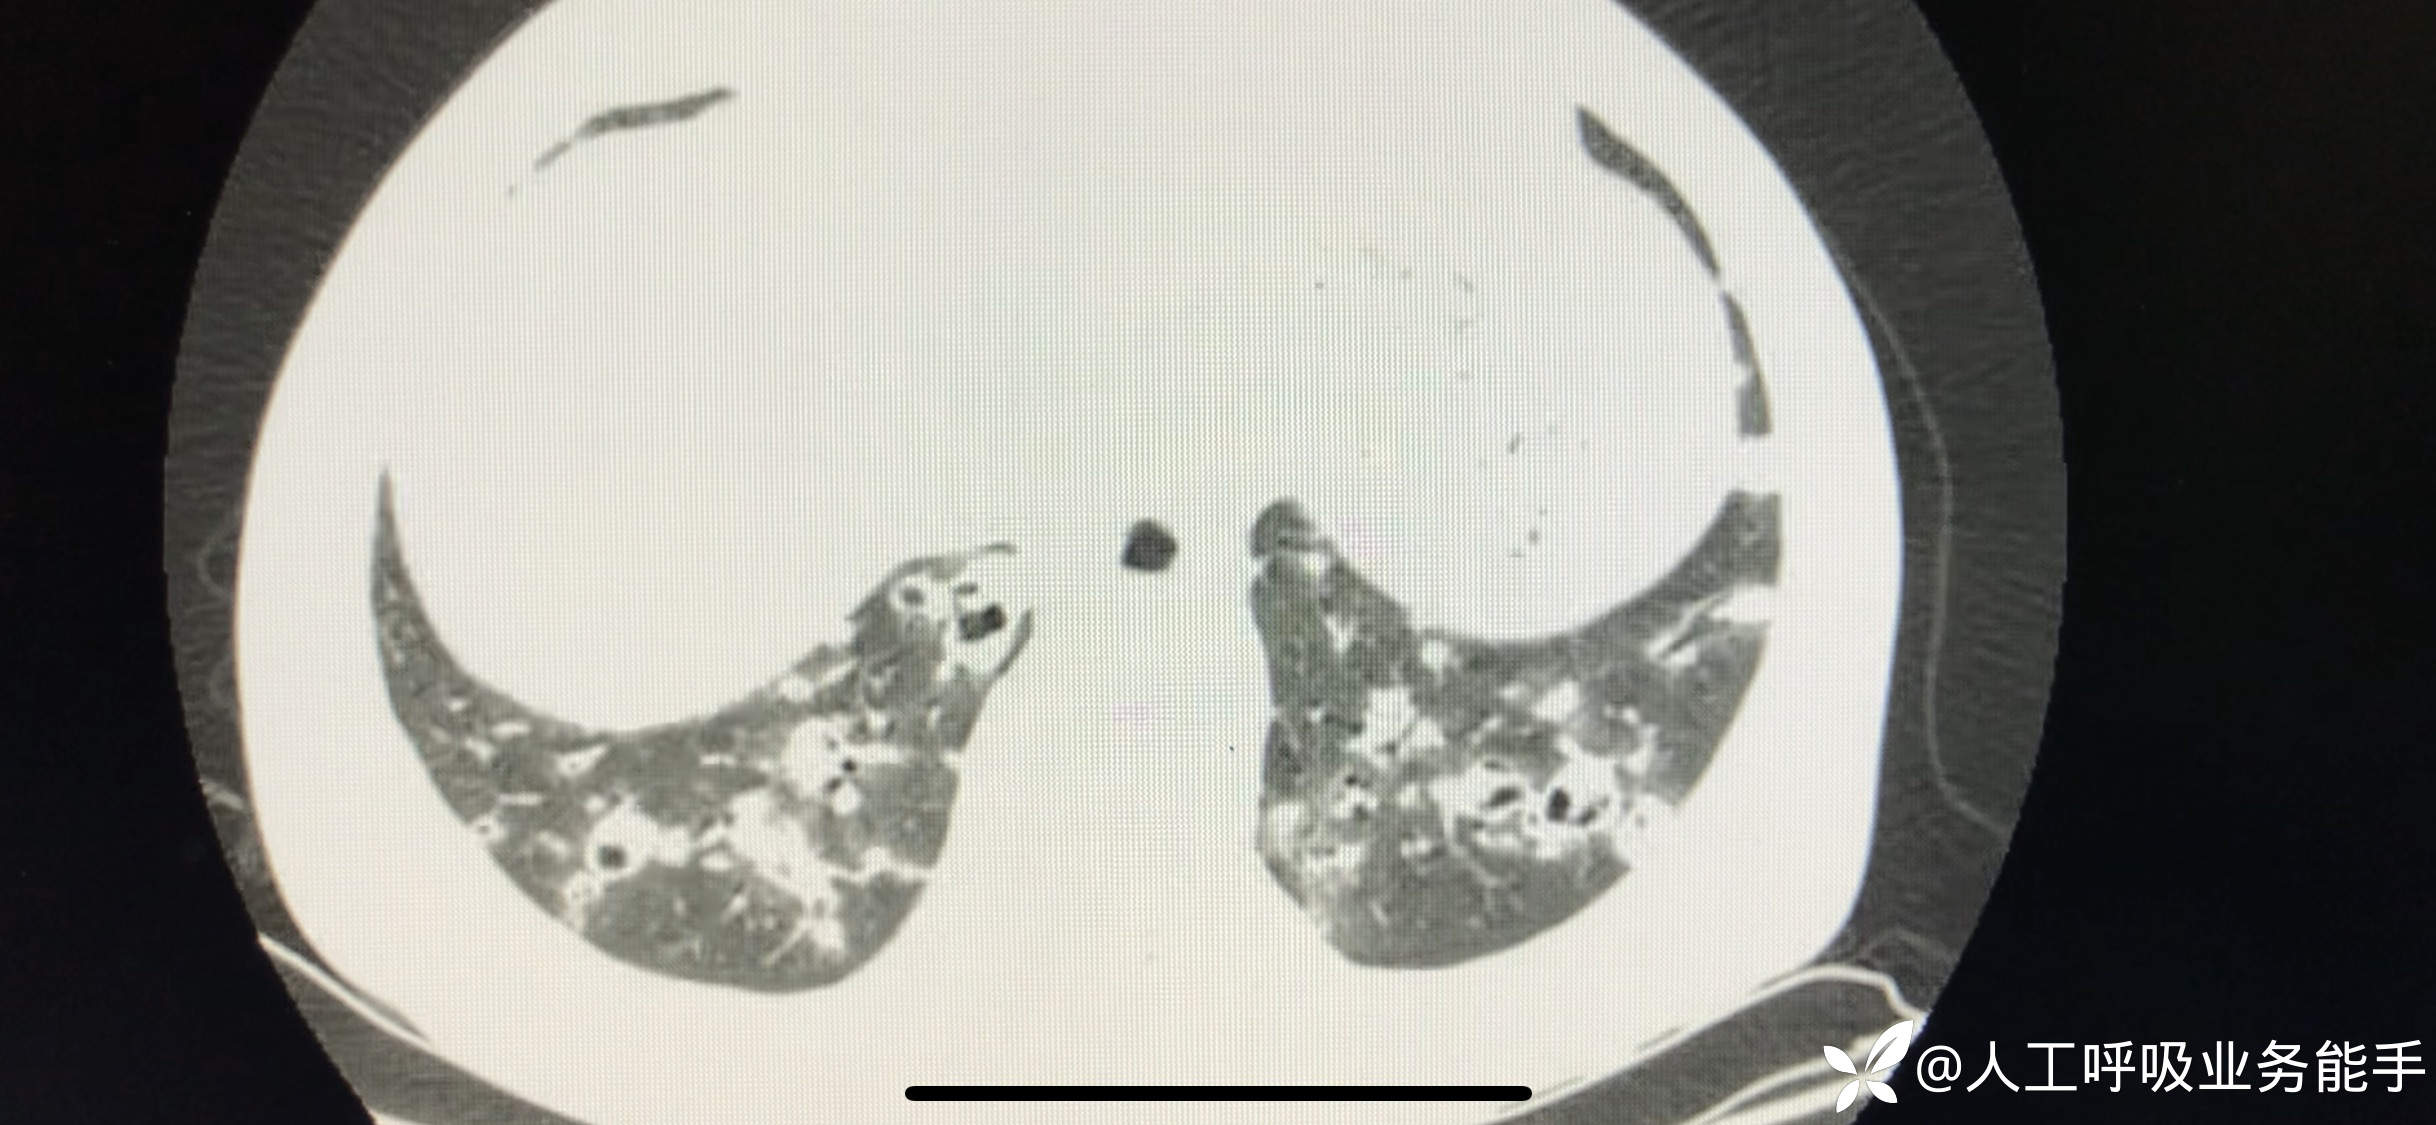

初诊影像: